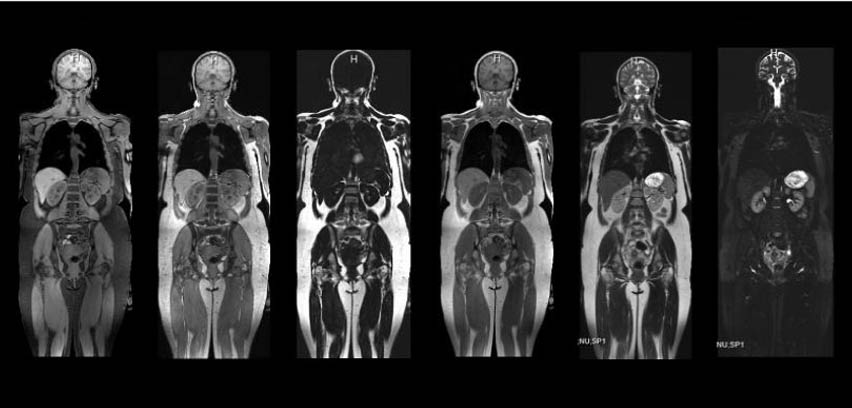

More comfortable. Higher quality images. MRls in half the time. Desert Imaging now offers state-of-the-art 3-Tesla MRI exams on our new ultra-wide bore uMR OMEGA™ system that delivers unrivaled speed, quality, and comfort to El Pasoans.

EXCEPTIONAL IMAGE QUALITY

- Best-in-class homogeneity and gradient performance

- World’s largest field of view (60x60x50 cm)

- Motion insensitive sequences for clearer images